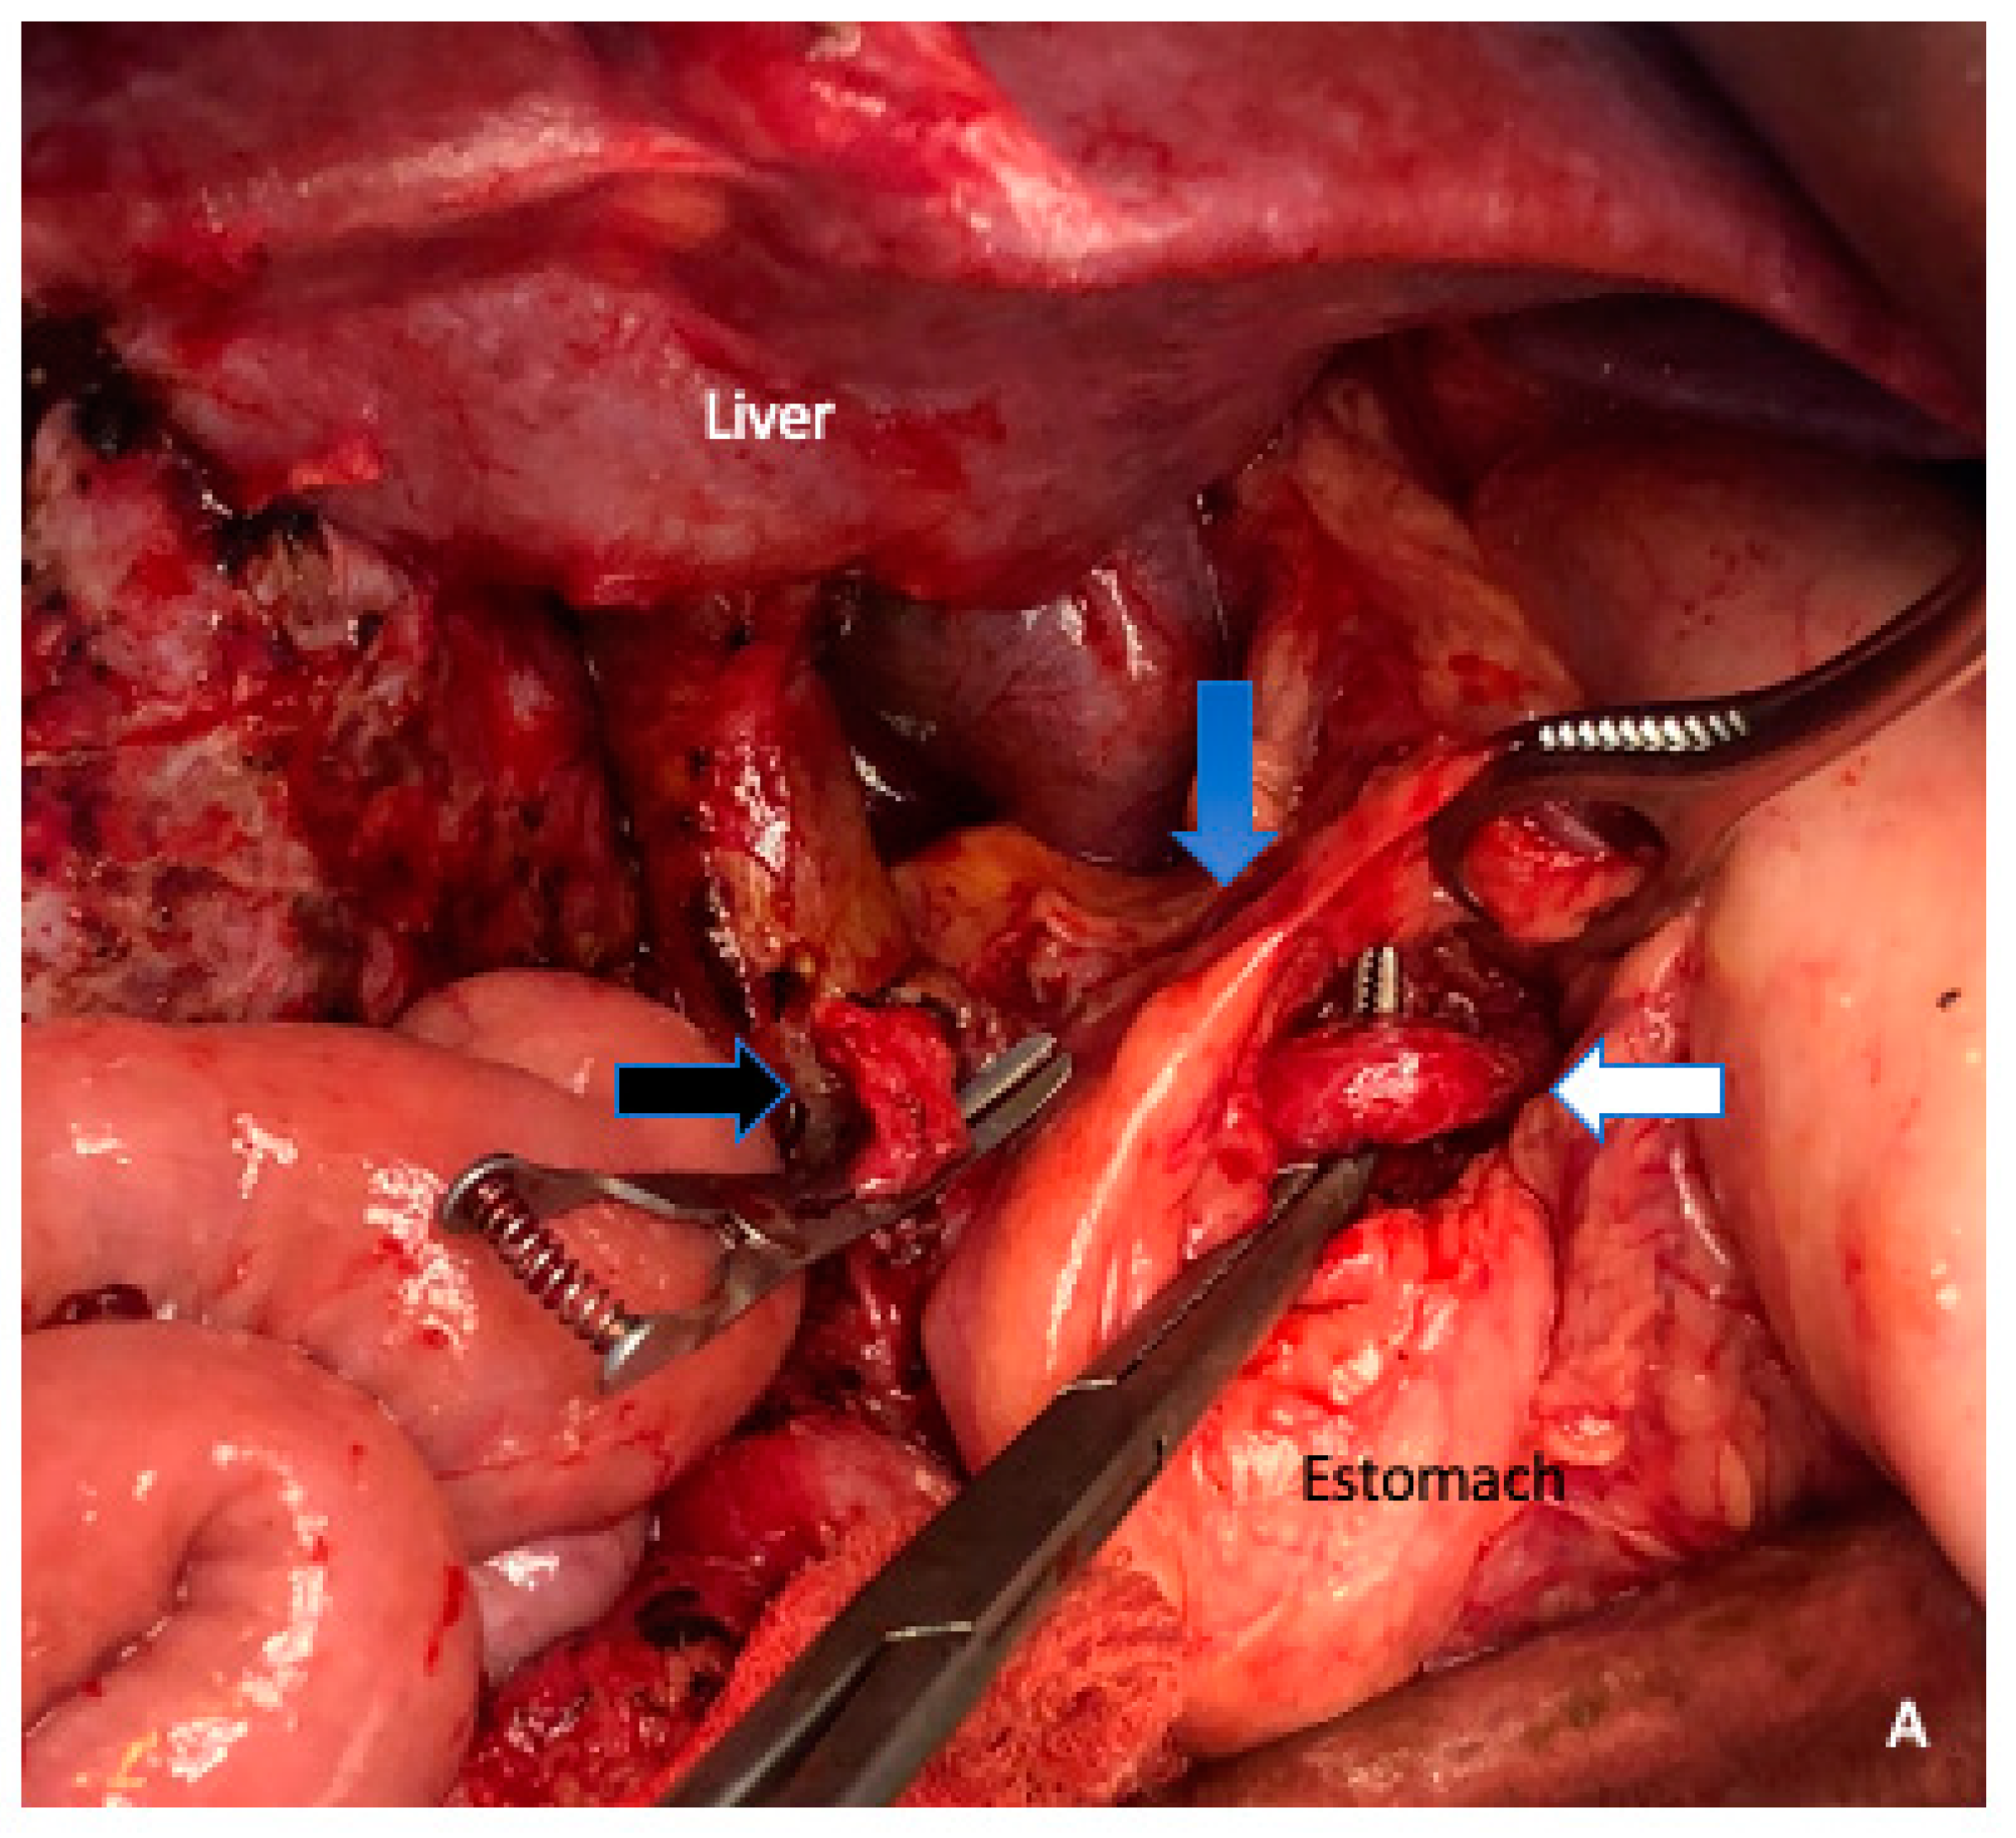

6. Arterial Resection